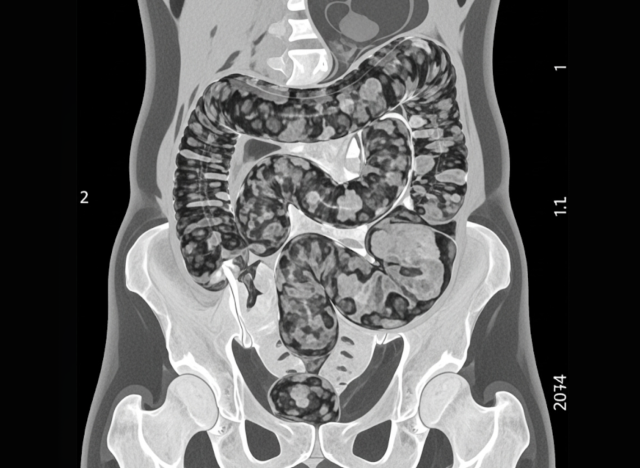

CT 검사 결과 A씨는 대장이 굳은 대변으로 가득 차 스스로 배변이 어려워지는 심각한 변비 상태인 '대변 매복'으로 진단받았다.

CT 검사 결과 A씨는 대장이 굳은 대변으로 가득 차 스스로 배변이 어려워지는 심각한 변비 상태인 '대변 매복'으로 진단받았다. 특히 S자 결장은 지름이 약 15㎝까지 비정상적으로 팽창해 내시경 장비가 들어가지 못할 정도로 장이 막혀 있었다.